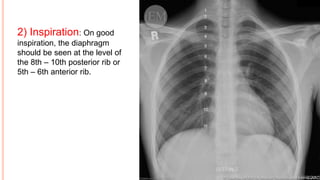

2) Inspiration: On good

inspiration, the diaphragm

should be seen at the level of

the 8th – 10th posterior rib or

5th – 6th anterior rib.

2) Inspiration: Ongood inspiration, the diaphragm should be seen at the level of the 8th – 10th posterior rib or 5th – 6th anterior rib.

• #22 The chest x-ray shows adequate inspiration.